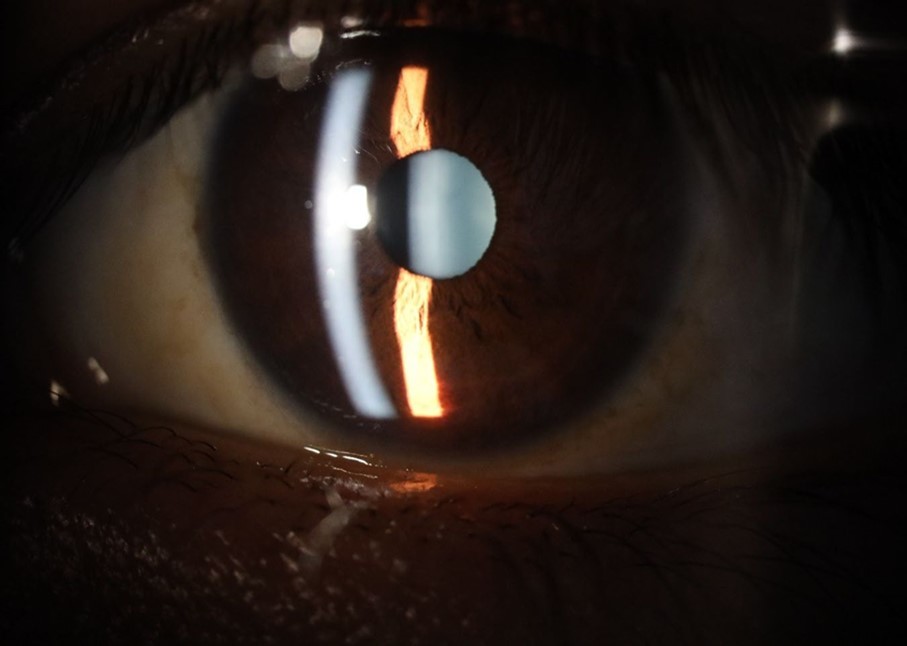

Figure 25.Mirror reflection of the affected eye (right side), with good appearance. This indicates that the transparent media of the eyeball (Cornea, anterior chamber, lens, and vitreous) are in good condition.

Figure 26.The macrograph of the anterior segment of the right eye (affected) shows very good transparency of the cornea, anterior chamber, lens, and vitreous.

++/++

Figure 31.The photograph of the right eye shows an almost normal mirror reflection, as well as a better pupillary dilation.

Figure 32.The macro photograph of the right eye shows us a cornea, anterior camera, and crystalline lens in very good condition.